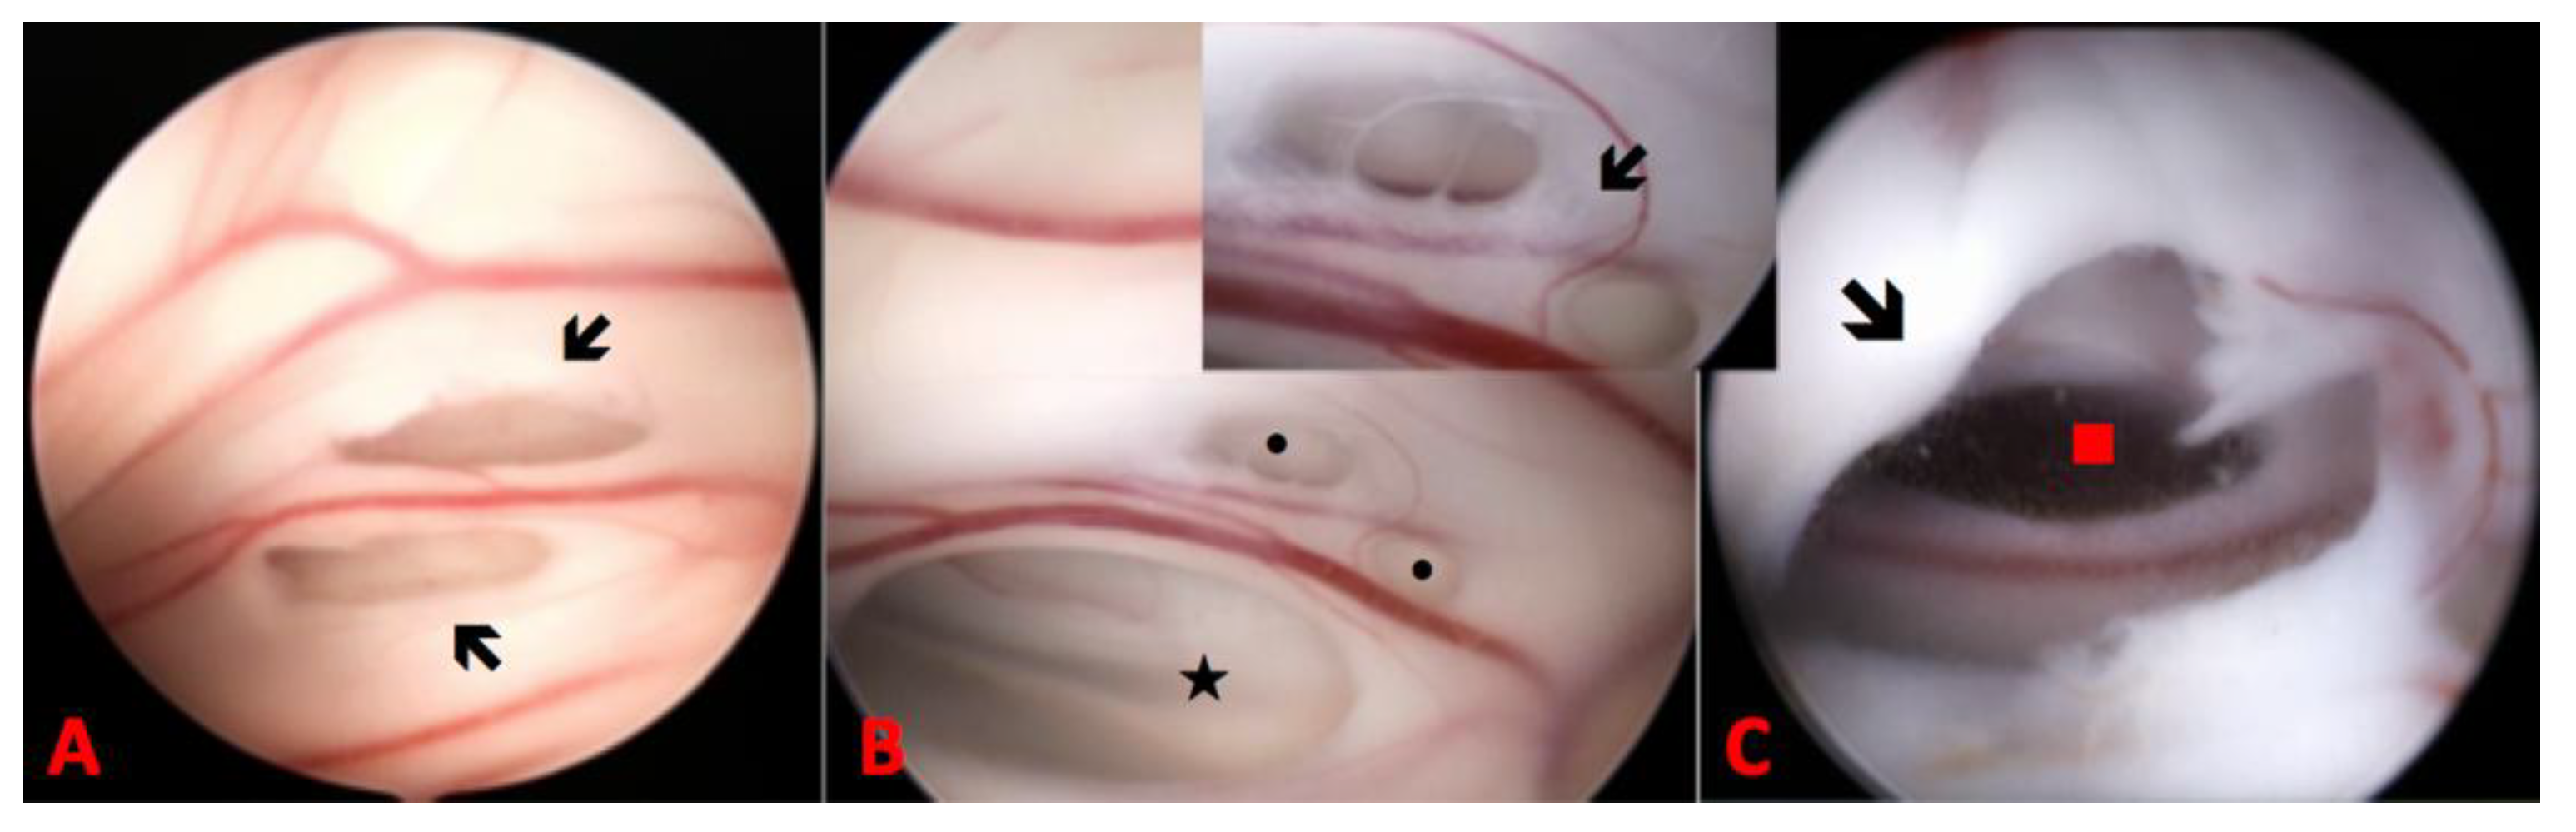

2. Case Report

| movie 1 | 1st surgery |

| movie 2 | 2nd surgery |